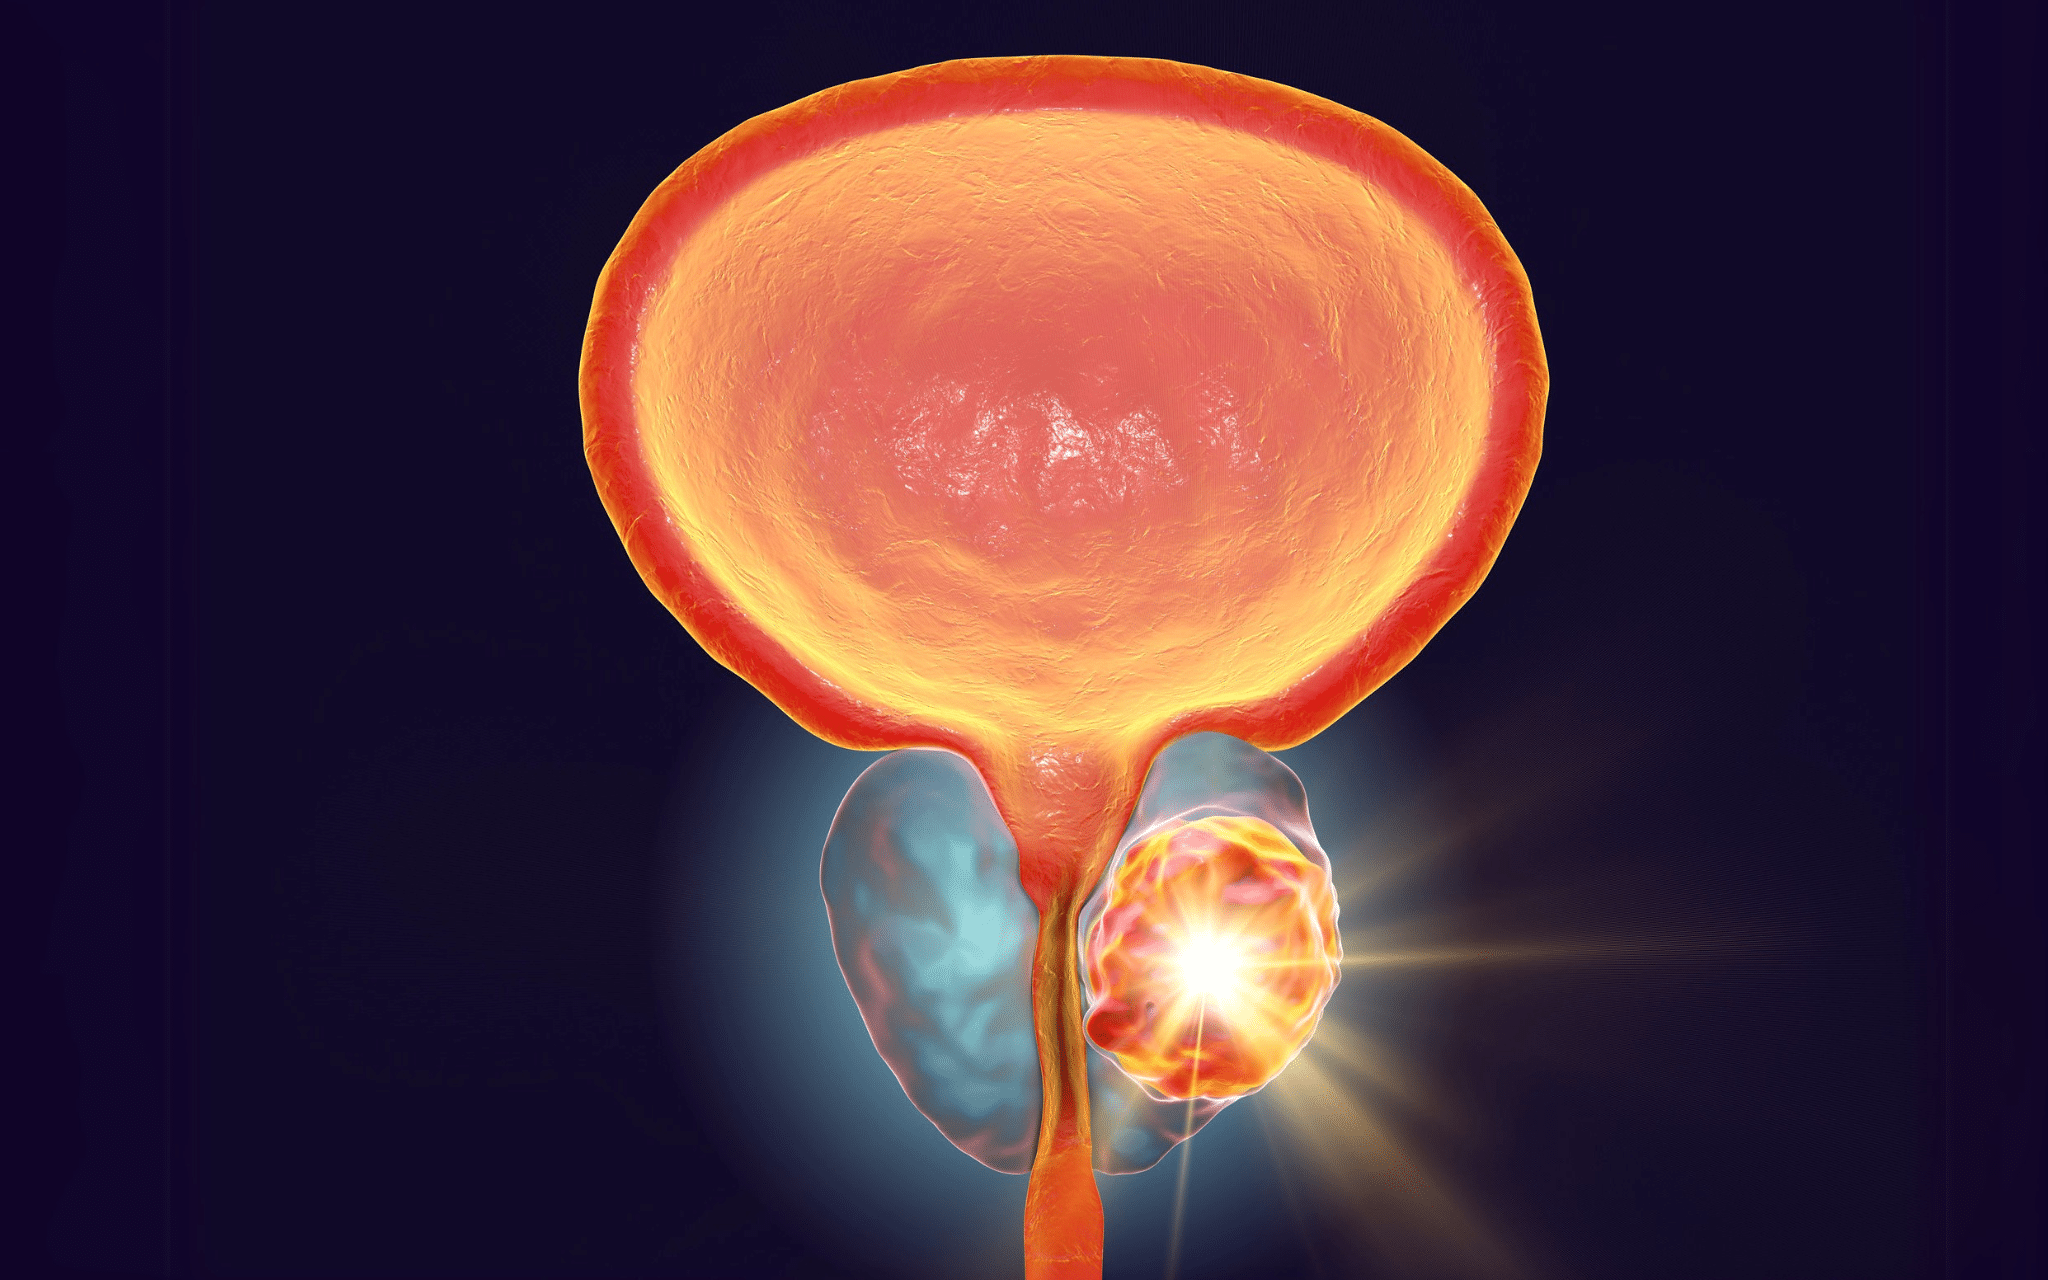

Радикальная простатэктомия

Радикальная простатэктомия предполагает полное хирургическое удаление предстательной железы вместе с прилежащими тканями, семенными пузырьками, а при необходимости и лимфатическими узлами. Данный подход рекомендуют в случаях злокачественных опухолей, когда своевременное полное удаление пораженных участков является ключевым фактором предотвращения метастазирования и рецидива. Главная цель операции – длительная ремиссия или полное выздоровление пациента, а также сохранение функций мочеиспускания и, по возможности, половой активности.